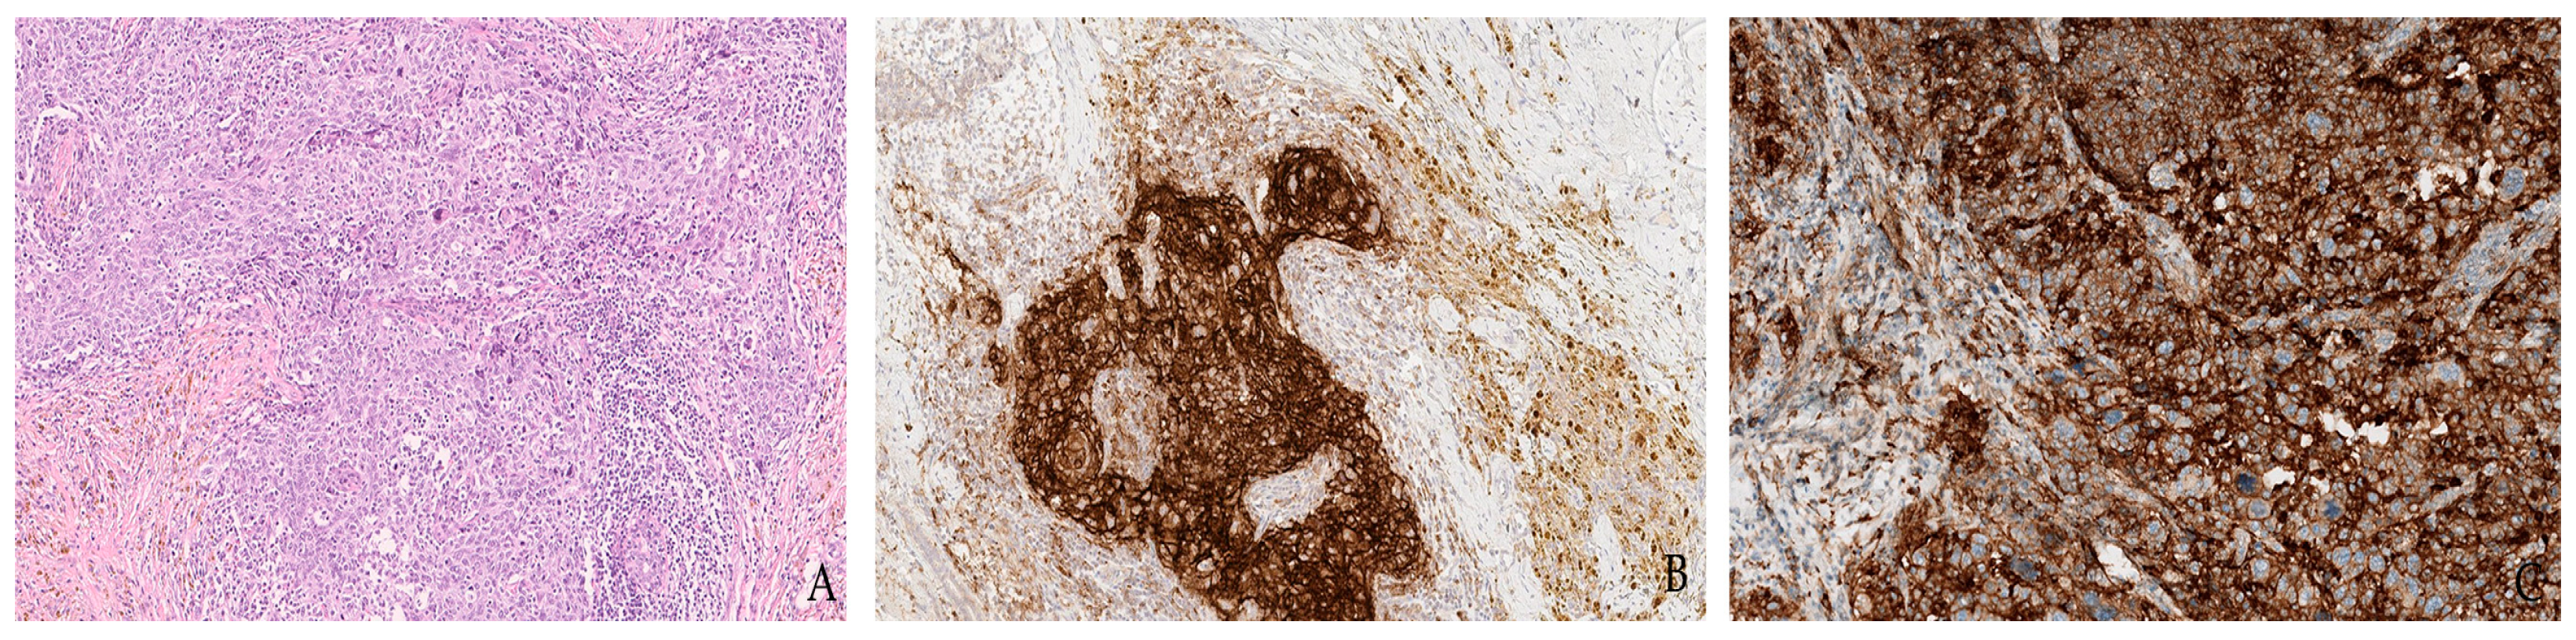

- Luchini, C.; Cros, J.; Pea, A.; Pilati, C.; Veronese, N.; Rusev, B.; Capelli, P.; Mafficini, A.; Nottegar, A.; Brosens, L.A.A.; et al. PD-1, PD-L1, and CD163 in pancreatic undifferentiated carcinoma with osteoclast-like giant cells: Expression patterns and clinical implications. Hum. Pathol. 2018, 81, 157–165. [Google Scholar] [CrossRef] [PubMed] [Green Version]